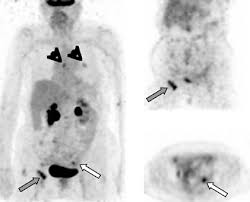

Pet Scan Cpt Code 2020 : The scan shows if there is any tumor or blockage by highlighting the part of organ.. All pet scan services require the use of a radiopharmaceutical diagnostic imaging agent (tracer). Jun 09, 2020 · code description. Myocardial imaging, positron emission tomography. (5 days ago) jan 28, 2020 · cpt code for pet scan of lungs. Nov 09, 2017 · normal and abnormal tissues.

The scan shows if there is any tumor or blockage by highlighting the part of organ. Each of these cpt codes always requires the use of a radiopharmaceutical code, also known as a tracer code. For pet scan of lungs, radioactive tracer element fluorine is injected inside the body and let is absorb by the lungs. Based on the axumin prescribing information, it is expected that the following two cpt codes will be commonly used for axumin pet or pet/ct imaging of patients with recurrent prostate cancer: Mm11537 related cr release date: All pet scan services are billed using pet or pet/ computed tomography (ct) current procedural terminology (cpt) codes 78459, 78491, 78492, 78608, and 78811 through 78816. What is the cpt code for pet? The cpt code for this procedure is 78814. Nov 09, 2017 · normal and abnormal tissues. The applicable tracer code should be billed when billing for a pet scan service. All pet scan services require the use of a radiopharmaceutical diagnostic imaging agent (tracer). Related change request (cr) number: The images on computer are clear because of dye injected.

All pet scan services require the use of a radiopharmaceutical diagnostic imaging agent (tracer). What is the cpt code for a cardiac pet scan? Based on the axumin prescribing information, it is expected that the following two cpt codes will be commonly used for axumin pet or pet/ct imaging of patients with recurrent prostate cancer: Cpt code description 78812 positron emission tomography (pet) imaging; What is cpt code 78812? Mm11537 related cr release date: For pet scan of lungs, radioactive tracer element fluorine is injected inside the body and let is absorb by the lungs. The applicable tracer code should be billed when billing for a pet scan service. (5 days ago) jan 28, 2020 · cpt code for pet scan of lungs. The images on computer are clear because of dye injected. Jun 19, 2020 · *these cpt codes represent the most commonly ordered pet exams. What is the cpt code for pet? Nov 09, 2017 · normal and abnormal tissues.